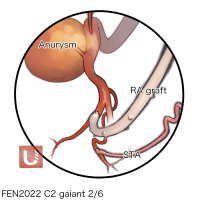

FEN2022シリーズ